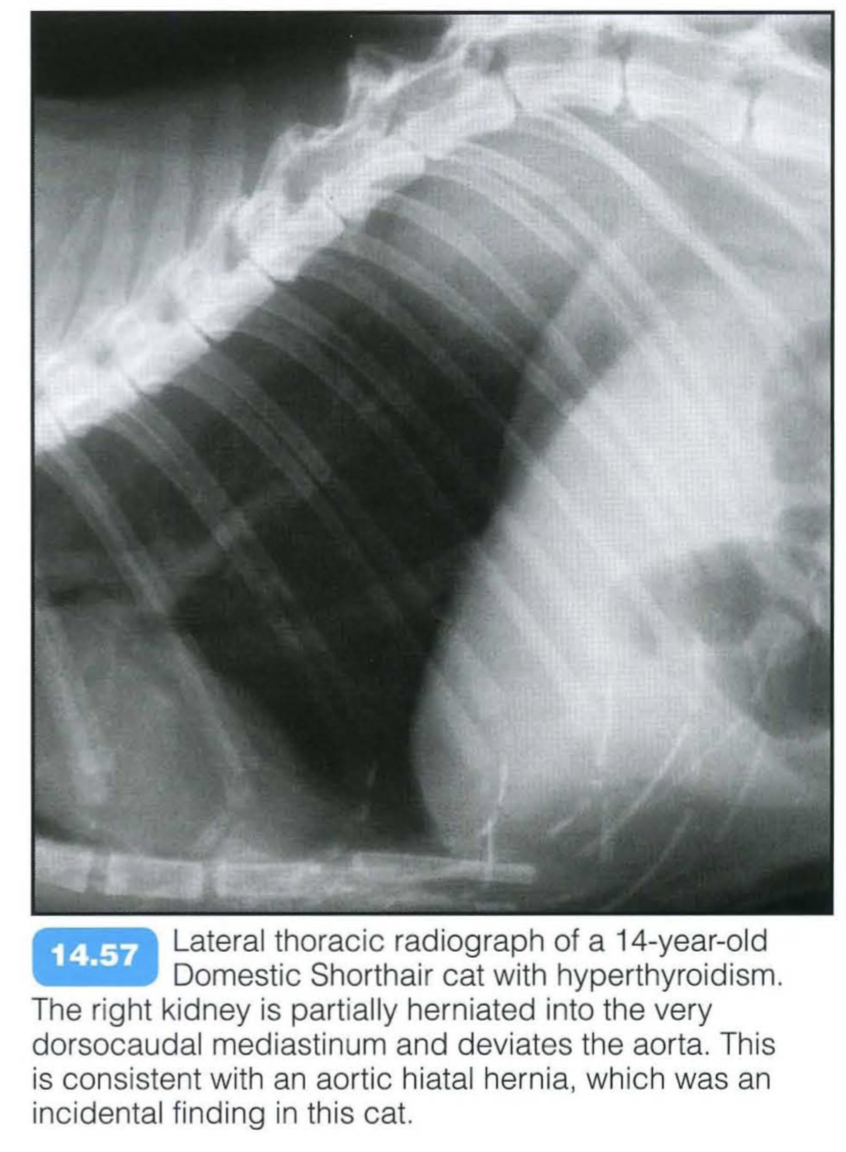

Aortic Hilar Hernia

The aortic hilus is the only diaphragmatic opening that connects the mediastinum with the retroperitoneal space. Free mediastinal gas can pass through the hilus and enter the retroperitoneal space relatively easily. If defects in this hilus exist, retroperitoneal organs such as the adrenal glands and kidneys can prolapse into the mediastinum. Intramediastinal kidneys are rare in dogs and cats and are usually detected incidentally.

Radiographic findings include: